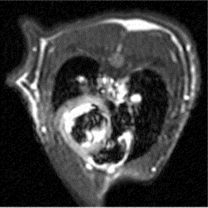

生理学的評価の例

ラット心臓・脳脊髄液のシネ画像

トリガーからパルス起動までの時間を変化させ、それを編集することで心臓が動いているようなシネ画像を撮ることもできます。